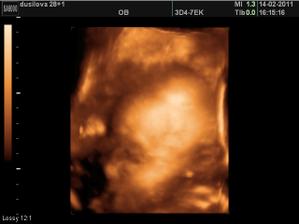

Ve 28tt nám paní doktorka na 3D ukázala krásnýho chlapečka i s jeho pýchou 🙂 Na 99,9% čekáme chlapečka - Tadeáška. Jsem hrozně moc šťastná, že nám vyšlo to co jsme od začátku chtěli - mít starší dcerku a mladšího syna! Tak teď už to jen zdárně doklepat do konce 😀